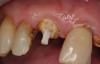

A Class IN maxillary bicuspid was previously restored with a fiber post and an all-porcelain crown (Figure 1). The forces of the oral environment resulted in fracture of the fiber post and crown failure. The remaining fiber post in the root was removed, and anti-rotational areas were prepared for a cast post (Figure 2). A gold cast post was constructed at a dental laboratory, using an indirect technique (Figure 3). A porcelain-fused-to-metal (PFM) crown was constructed with a bevel finish to provide a ferrule and reduce forces on the post (Figure 4 and Figure 5).

Figure 3  Cast post to restore the second bicuspid.

Figure 3